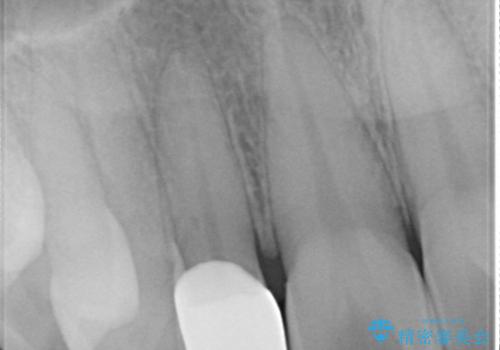

【オールセラミッククラウン】矮小歯の治療

- 矯正治療で配列した矮小歯をオールセラミッククラウンで修復治療を行いました。

すごく自然な仕上がりになり満足していただきました。

オールセラミッククラウンは、隣の歯に合わせて色調を調整することができるため非常に綺麗に仕上がります。